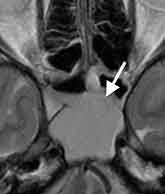

篩骨洞炎

24歳男性、両側の目の奥の痛みで受診。頭部MRI検査で篩骨洞の炎症を認めました。

副鼻腔炎による頭痛